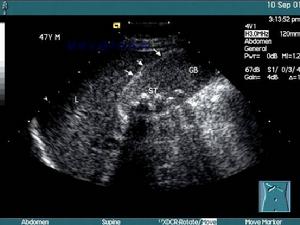

急性膽囊炎--B超當醫生檢查病人的腹部時,可以發現右上腹部有壓痛,並有腹肌緊張,大約在1/3的病人中還能摸到腫大的膽囊。化驗病人的血液,會發現多數人血中的白細胞計數及中性白細胞增多。B超檢查可發現膽囊腫大、囊壁增厚,並可見結石堵在膽囊的頸部。

3.B型超聲檢查,膽囊增大,囊壁增厚,可能可看到結石的影像。

3.B超檢查示膽囊增大,壁厚>3.5mm,內有強光團伴聲影。